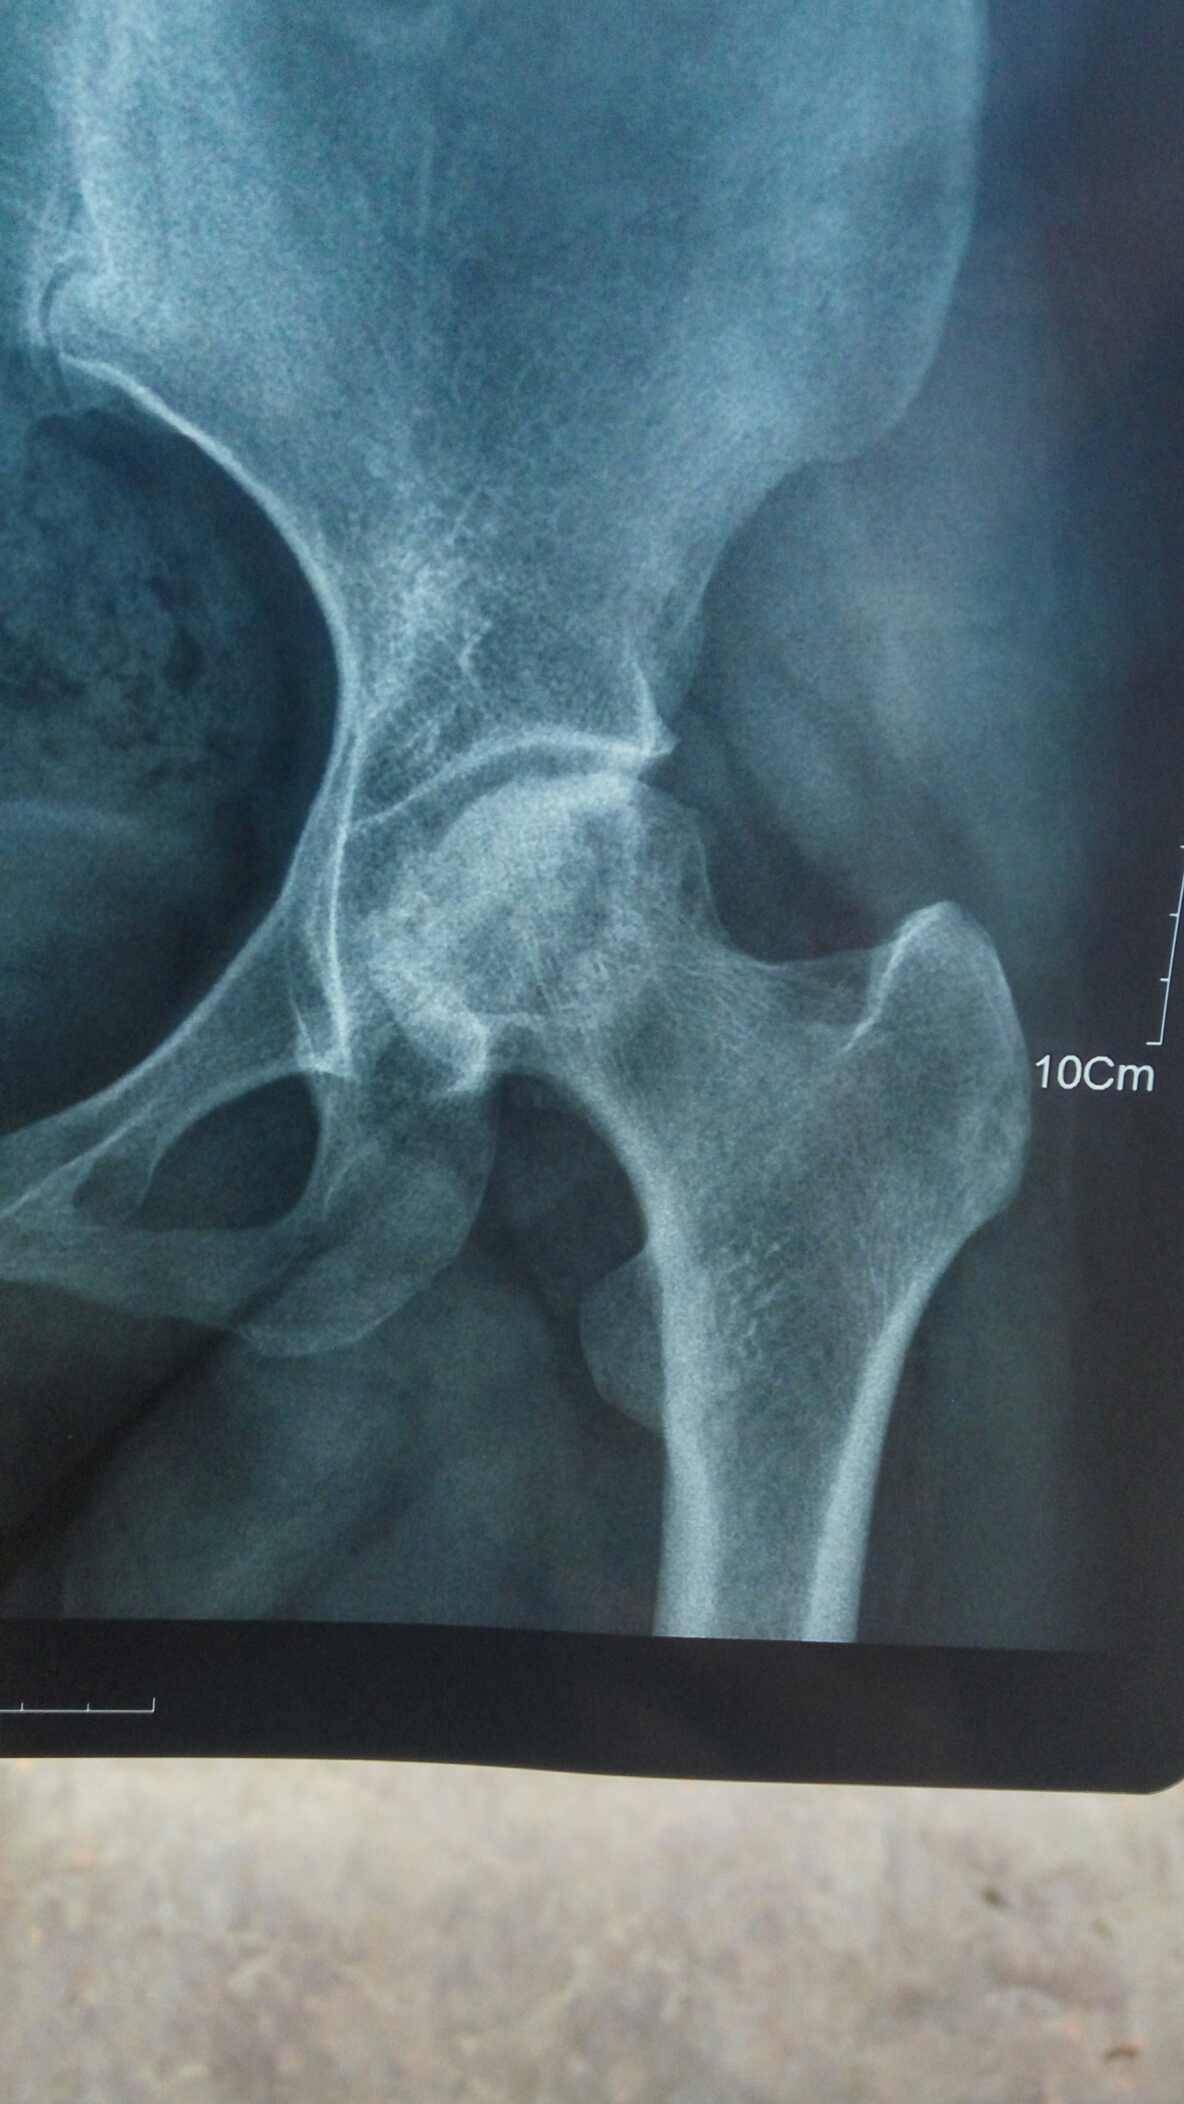

前几天复查一切都还好,就是腿好像比上次严重点,这半年太不注意了走路太多。有会看片子的吗?帮我看看骨质怎么样?前两张是刚拍的,后面一张是去年的。

骨坏了股骨头处一般骨质都有点不好

你右边比较严重啊?有点塌陷了

骨密度看不太出来,股骨头外观形态没太大变化。